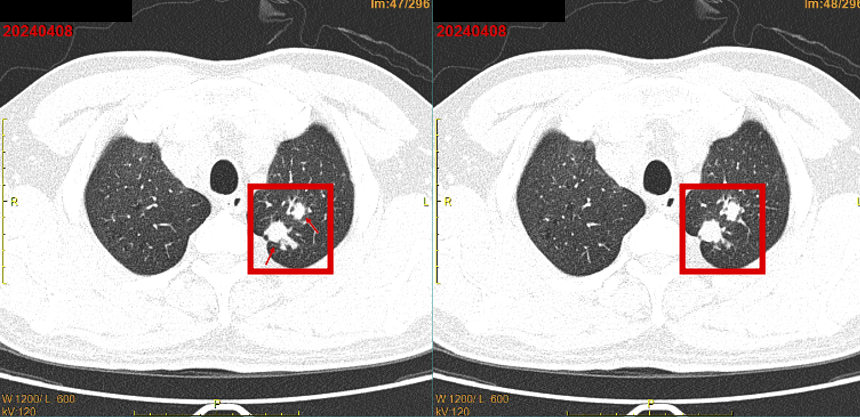

患者2024年2月感冒后出现咽痛、咳嗽、咳黄色粘痰,偶有痰中带血(7-8次/天,晨起明显),伴胸闷、活动后稍气促,偶有头晕、盗汗,未重视。2024年3月因咯血增多于当地医院就诊,胸CT提示肺占位。2024-04-08我院全身PET/CT示:

1.左肺上叶尖后段高代谢实性结节(2个结节融合),考虑周围型肺癌;

2.左侧肺门、纵隔(2R、3A、4L、6组)多发淋巴结转移;

3.左侧肾上腺结合部增粗,代谢增高,考虑转移瘤。

18F-FDG全身显像:左肺上叶尖后段高代谢实性结节(较大1.9×1.8×2.4cm),考虑周围型肺癌;左侧肺门、纵隔多发淋巴结转移;左侧肾上腺结合部稍粗,代谢增高,考虑转移瘤。

2024-04-08(初诊)vs 2025-03-07(复查)PET/CT:

左肺上叶尖后段实性结节体积缩小(较大约0.8×0.8×1.1cm vs 原1.9×1.8×2.4cm);

左肺门、纵隔多发淋巴结转移瘤体积缩小;

左侧肾上腺结合部增粗程度减轻。